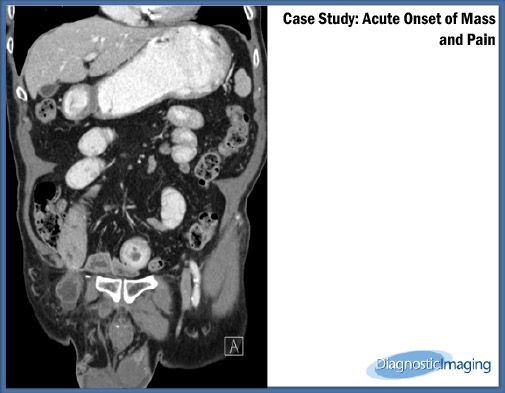

Case History: 82-year-old male presented with acute onset of right inguinal region mass.

Case History:Â 82-year-old male presented with acute onset of right inguinal region mass and pain and generalized abdominal pain.